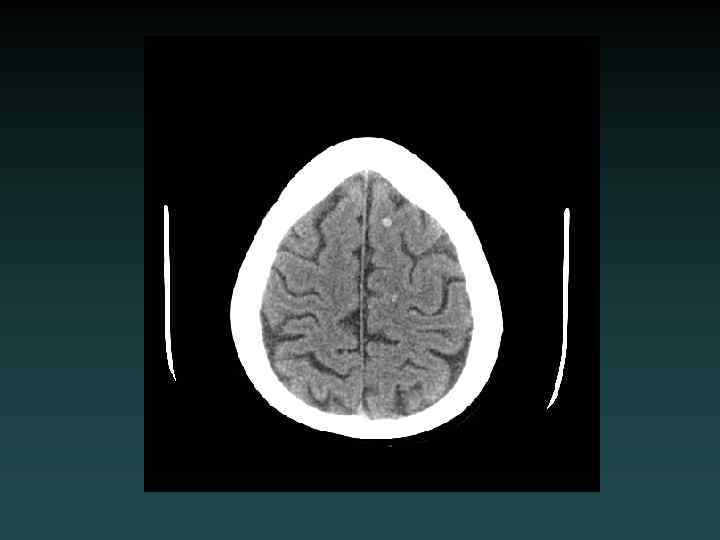

Subcortical Injury • Shear-Strain forces – Penetrating vessels – Axonal injury • “Tip of the iceberg” – Consider MRI • Neurological deficits may be out of proportion to degree of injury visible on CT

MRI: Diffuse Axonal Injury